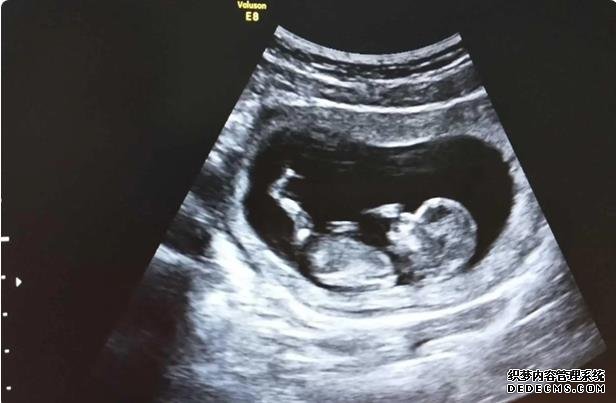

10天回医院抽血我怀上了,我既然怀上了,血值475.这会我还是不相信我觉得没那么容易,回家继续安胎,14天后一超,有胎芽了,存活了?继续回家安胎7天二超,胎儿一切正常,再回家安胎,14天三超胎儿长的很好!毕业的时候怀孕差不多两个月!然后回家安胎第一次产检胎儿一切正常,每次看到b超图那个小人儿心里那感觉,所有的报告正常,应该好多像我这样的人都会对着报告傻笑!心里那开心!开心接下来就是等早唐报告一个礼拜出来,报告结果一切正常!回家安心等中唐啦!其实等待的过程心里都是很担心,怕宝宝哪里不正常的!我真后悔当初不一早直接做试管!